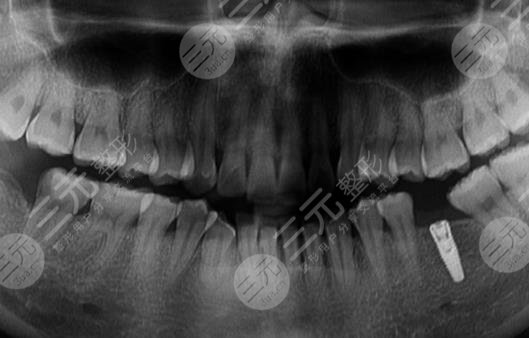

到醫(yī)院進(jìn)行面診的時(shí)候,醫(yī)生先讓我咬了牙齒的模型,然后又拍了牙片,選擇了牙齒的種植體,一星期之后,我來到了醫(yī)院進(jìn)行種植牙。整個(gè)種植牙的過程是很快的,而且因?yàn)榇蛄司植縨z也沒有任何的感覺。大家現(xiàn)在可以看到我的種植牙是十分成功的,而且看上去十分的潔白,跟周圍的牙齒形成了鮮明的對(duì)比。